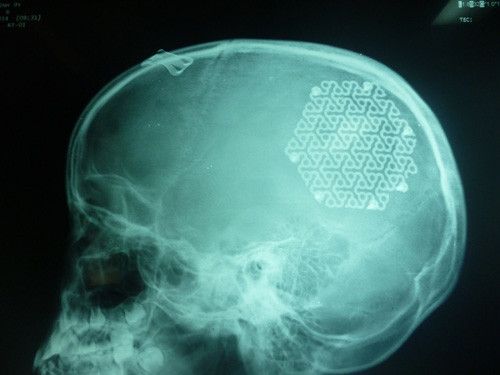

Với phương pháp tạo hình hộp sọ bằng tấm kim loại (titanium), các bác sĩ Bệnh viện Hữu nghị Việt Nam - Cu Ba Đồng Hới đã phẫu thuật tái tạo thành công hộp sọ cho bé gái 9 tuổi ở xã Quảng Sơn (Quảng trạch, Quảng Bình).

Hộp sọ được tái tạo bằng tấm kim loại. Ảnh: Long Nhật.

Sau 3 tháng, khi sức khỏe ổn định, các bác sĩ mới quyết định tái tạo hộp sọ cho cháu để bảo vệ mô não bên dưới và đảm bảo tính thẩm mỹ.

Theo các chuyên gia, thường thì khi bị chấn thương sọ não, bệnh nhân sẽ được phẫu thuật lấy máu tụ, phần xương sọ lấy ra được bảo quản chuyên dụng sau một thời gian thì ghép trở lại cho bệnh nhân. Riêng với trường hợp của cháu bé này, vì xương sọ đã vỡ vụn nên các bác sĩ phải ghép sọ bằng vật liệu nhân tạo. Hiện sức khỏe cháu đã ổn định và đang được theo dõi, chăm sóc.